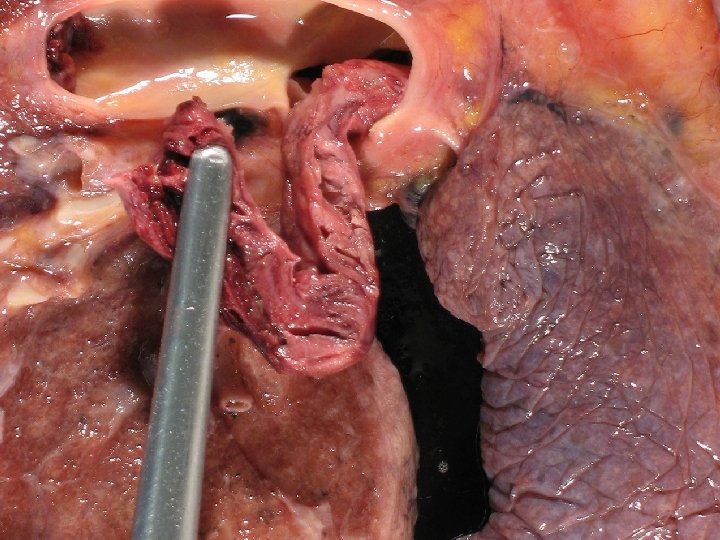

Lung with PE